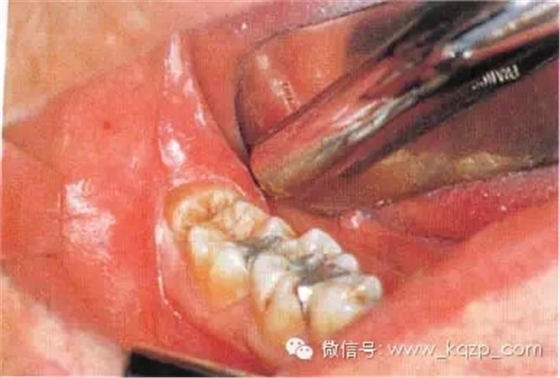

a第Ⅱ類,b分類中位阻生。左下頜第三磨牙阻生,位于黏膜下。磨牙后區(qū)切開后,作近中切口,使用12號刀片沿牙齦扇貝狀外形切透齦溝至牙槽嵴頂,避免將齦乳頭切除。圖中近中切口延長至第二前磨牙,便于翻瓣,更好地顯露磨牙后區(qū)的骨質(zhì)

b翻瓣后,阻生牙的(牙合)面位于第二磨牙頸部及其牙槽嵴頂均清晰可見。切割牙體前先去除舌側(cè)骨板以保護(hù)軟組織

c使用紡錘形的車針( Komet - H162A.314),顯露其最大周徑至釉牙骨質(zhì)界。車針末端應(yīng)進(jìn)入牙槽窩內(nèi)壁

d 分牙前應(yīng)認(rèn)真確定分牙溝的位置:沿牙體長軸垂直(牙合)面至根分叉。用上述的車針分牙。切割至牙冠舌側(cè)時(shí)應(yīng)格外小心

e分牙已基本完成,遠(yuǎn)中牙片挺松后即可順利取出

f 遠(yuǎn)中牙片取出后即可拔除近中部分。術(shù)后應(yīng)注意牙槽嵴頂?shù)母叨?。保留頰側(cè)骨板很重要,它有利于牙槽窩和第二磨牙牙槽骨的完全重建

g 將皮瓣復(fù)位后,磨牙后區(qū)縫合2針,此處使用的是不可吸收的聚硅酮絲線(4—0)。第一、二磨牙之間縫合1針,以維持楔狀隙內(nèi)齦乳頭的位置并確保迅速的愈合。輕壓組織至少2 min,使骨膜和骨皮質(zhì)、牙齦和牙骨質(zhì)粘連復(fù)位。作用于軟組織的壓力還能排出氣泡形成良好的血凝塊

h只要有根分叉且近中傾斜程度不大、車針能夠順利進(jìn)入,沿牙體長軸進(jìn)行的正中切割就能順利進(jìn)行。該牙的根間孔尚未完全閉合